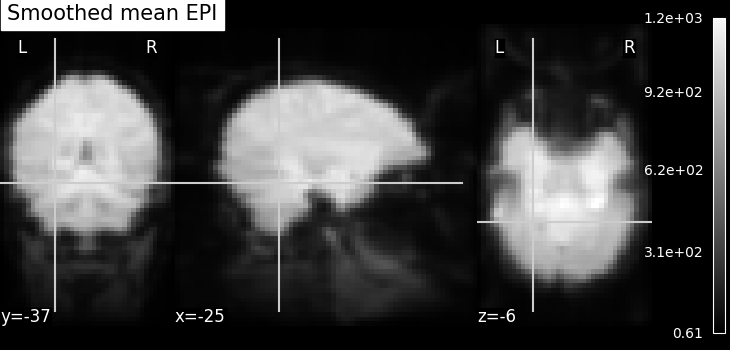

Smoothing: Functional MRI data have a low signal-to-noise ratio.

When using methods that are not robust to noise, it is useful to apply a

spatial filtering kernel on the data. Such data smoothing is usually applied

using a Gaussian function with 4mm to 12mm

full-width at half-maximum (this is where the FWHM

comes from). The function smooth_img accounts for

potential anisotropy in the image affine (i.e., non-indentical

voxel size in all the three dimensions). Analogous to the

majority of nilearn functions, smooth_img can

also use file names as input parameters.

fmri_img = image.smooth_img(fmri_filename, fwhm=6)

# Visualize the mean of the smoothed EPI image using plotting function

# `plot_epi`

from nilearn.plotting import plot_epi

# First, compute the voxel-wise mean of smooth EPI image

# (first argument) using image processing module `image`

mean_img = image.mean_img(fmri_img)

# Second, we visualize the mean image with coordinates positioned manually

plot_epi(mean_img, title="Smoothed mean EPI", cut_coords=cut_coords)